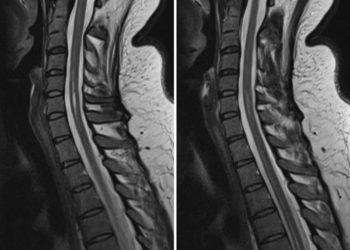

Verschleißerkrankungen der Halswirbelsäulenerkrankungen stellen eine häufige Ursache von ausgeprägten Schmerzzuständen des Nackens, Rückens und der Arme dar. Das können akute...